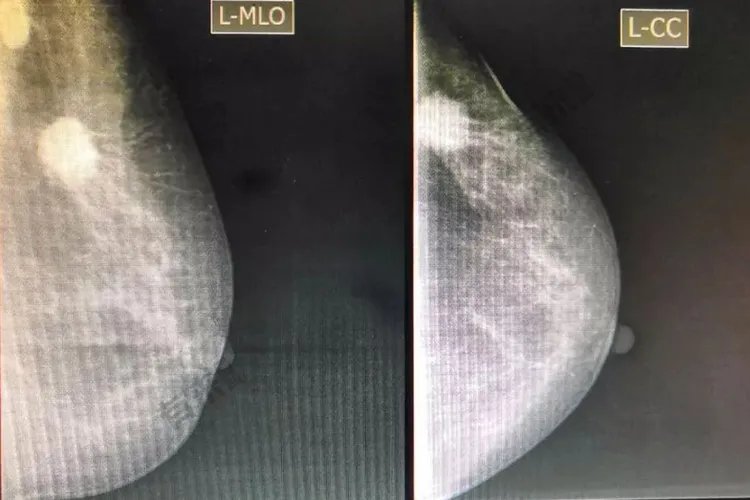

病因乳腺组织被位于皮下的浅筋膜所包绕,深浅筋膜之间由Cooper韧带相连。由于浅筋膜与皮肤相连,当乳腺癌侵及乳腺间的Cooper韧带使之缩短时,会牵拉皮肤,使局部皮肤凹陷,如同酒窝,称“酒窝征”。另外肿瘤直接与皮肤粘连也可能造成此种情况。治疗酒窝征的出现常提示乳腺癌存在的可能,一旦确诊要根据具体病情及时治疗。临床上常用的治疗方法有手术治疗、化学治疗、内分泌治疗、放射治疗、靶向治疗等。诊断乳腺癌酒窝征常根据乳房局部皮肤凹陷,如同酒窝这个典型特征进行诊断,同时可行体格检查,嘱患者上下活动患侧手臂,以便更准确的诊断。病史、体格检查以及乳腺超声、钼靶检查或MRI是临床诊断乳腺癌的重要依据。确诊乳腺癌,要通过组织活检进行病理检查。